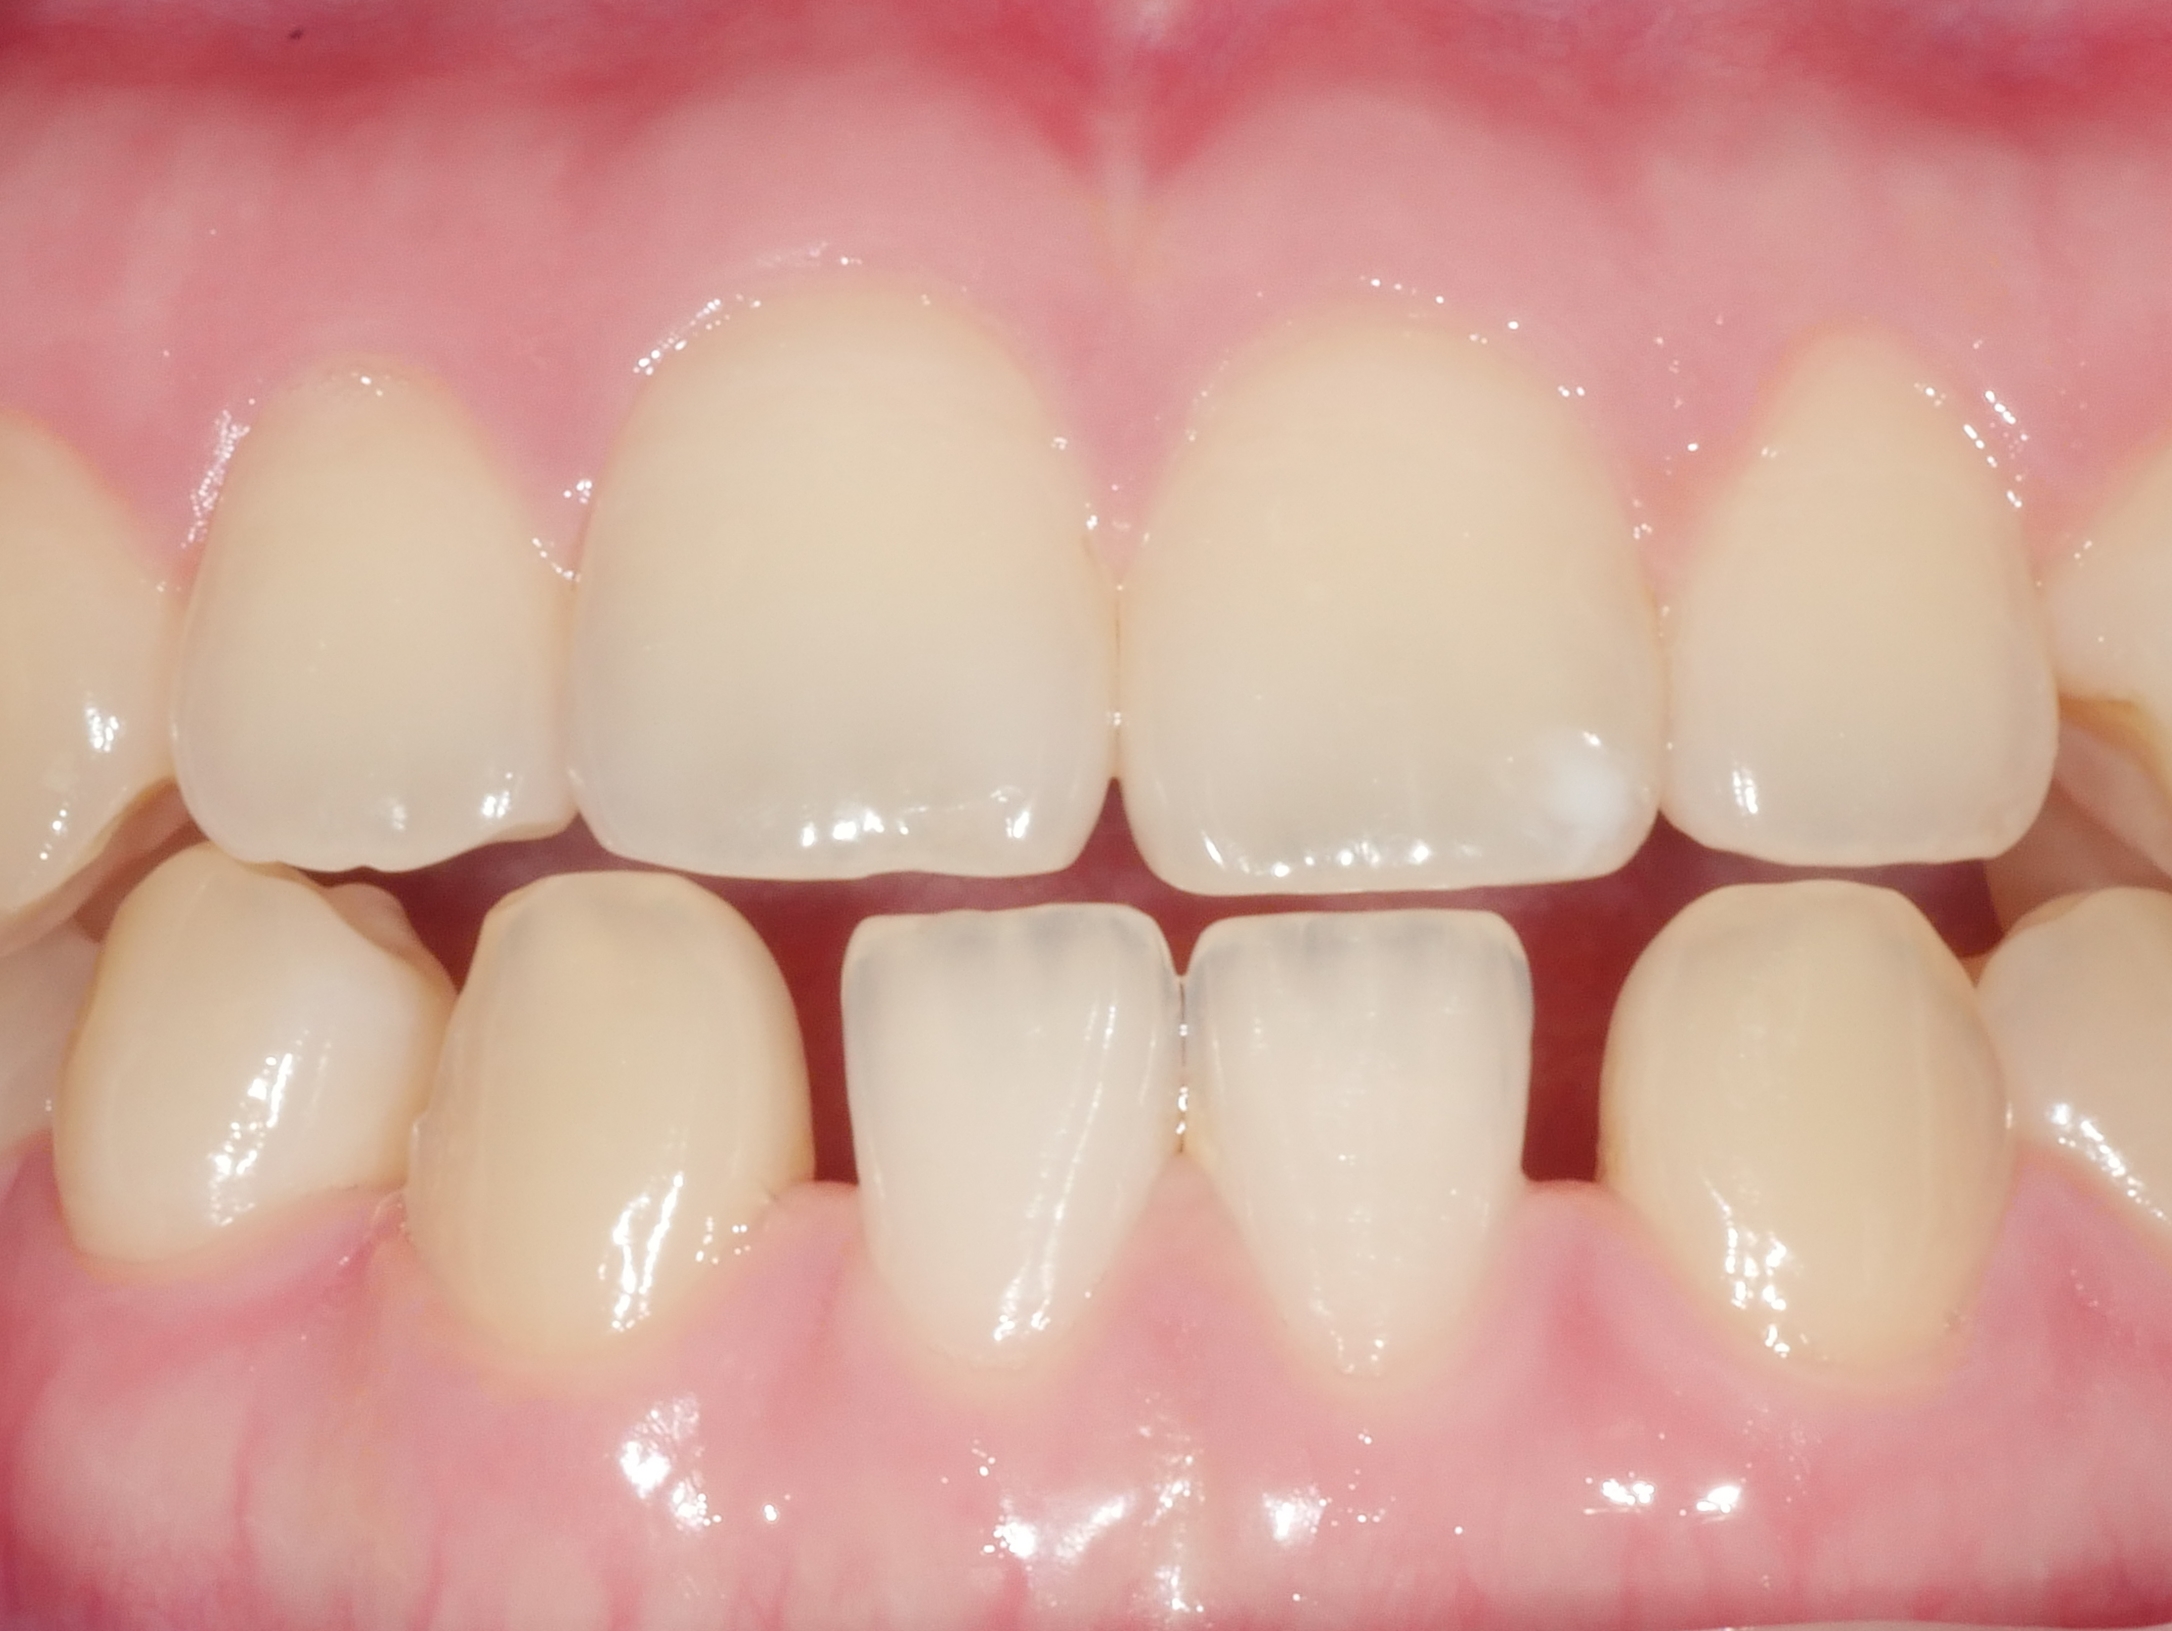

CASE.6 치아미백

치료전 2022.06.29 / 치료후 2022.07.06